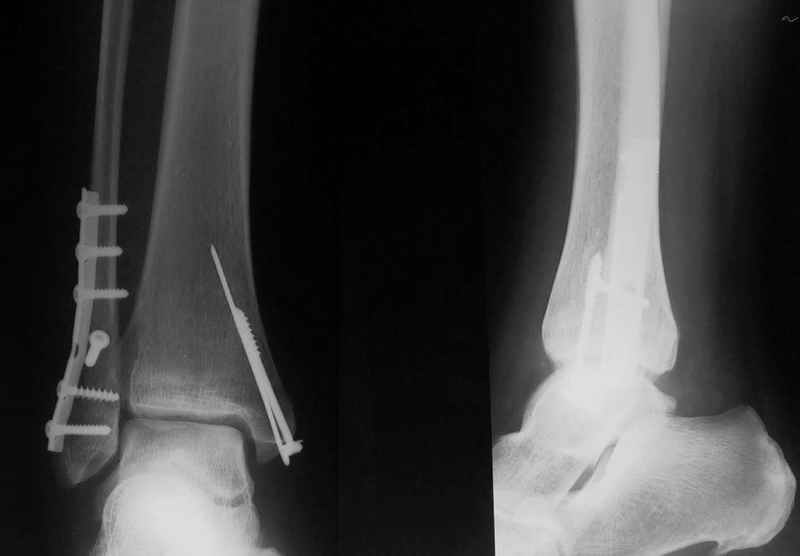

Стабильность г\ст сустава обеспечивается во-первых наружной лодыжкой (ключ), во-вторых задним краем б\б кости, в-третьих связками синдесмоза и межкостной мемраной, только в-четвертых медиальной лодыжкой (дельтовидной связкой. Это классика! А пяточной кости и плюсневых костей здесь нет! зачем их фиксировать? см. вложенный файл.

Коллега!Sorry,по-моему стоит провести винт через синдесмоз,а?Вроде бы контуры г\ст не совпадают,нет?Я дал бы компрессию на синдесмоз в положении полного разгиба стопы

1. Винт никогда не стоит проводить "через" синдесмоз. Если и проводить, то выше синдесмоза.

2. Межберцовый винт должен быть только позиционным и должен удерживать синбесмоз, а не компремировать его

3 Контуры девственны: талокруральный угол, суперпозиция, медиальное пространство. Что не совпадает?

Вообще, этот больной через 2 месяца после травмы в футбол играл.